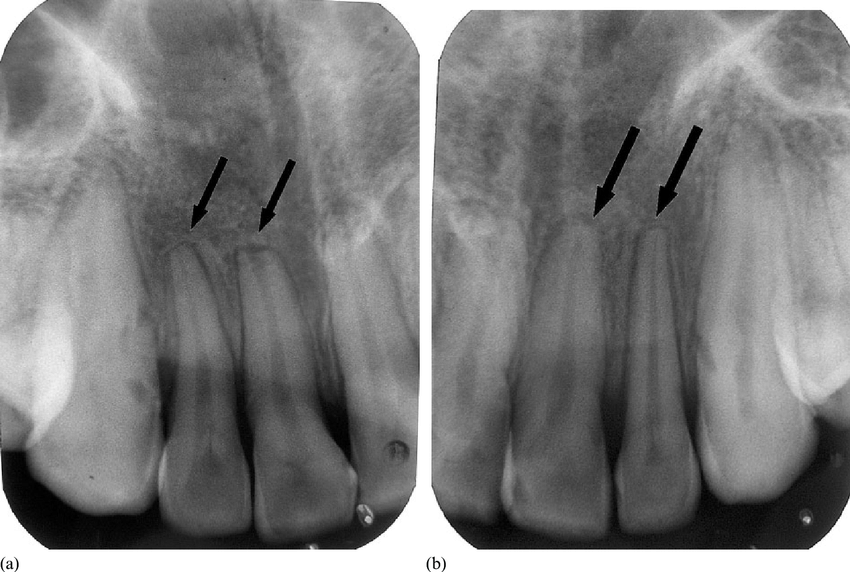

3. Méconnaître la bifurcation des canaux de l’incisive centrale inférieure

L’erreur : Considérer que l’ICI possède toujours un canal unique, rectiligne et cylindrique.

Conséquence : En endodontie, une bifurcation non dépistée peut conduire à un échec de traitement (canal non instrumenté, obturation incomplète).

La bonne pratique : Réaliser systématiquement une radiographie rétro-alvéolaire centrée avant tout traitement endodontique. La section aplatie de la racine dans le sens mésio-distal doit alerter sur l’éventualité de deux canaux.

Observation : Test de vitalité négatif sur la 41 (ICI). Pas d’abcès visible. La radiographie montre une légère opacification canalaire évocatrice de calcification partielle. La section de la racine est aplatie, ce qui laisse suspecter la présence de deux canaux.

Problématique : Traitement endodontique sur une dent réputée “simple”, mais potentiellement bi-canalaire.

Prise en charge : L’accès endodontique est réalisé avec prudence. Deux canaux sont identifiés : un vestibulaire et un lingual. Les deux sont instrumentés et obturés à la gutta-percha. Radiographie de contrôle confirmant le bon remplissage.

Résultat attendu : Guérison de la lésion périapicale dans les 6 à 12 mois. Dent conservée.

Point clé : La prévalence de deux canaux dans l’ICI est d’environ 20 %. La méconnaître est la principale cause d’échec endodontique sur cette dent.

Combien de canaux peut-on trouver dans une incisive centrale inférieure ? La majorité du temps, il n’y a qu’un seul canal. Cependant, dans environ 20 % des cas, deux canaux coexistent (un vestibulaire et un lingual) dans la même racine aplatie. Ce point est fondamental avant tout acte endodontique sur cette dent.